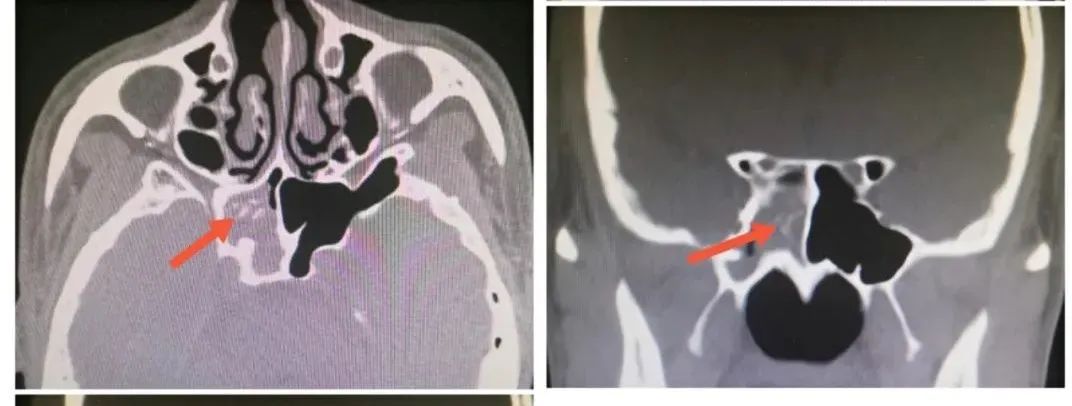

接诊陈艳娟医生耐心询问,全面评估并完善术前检查,排除手术禁忌后,于10月18日行了鼻内镜右侧蝶窦开放术,术中证实蝶窦内“蘑菇样”真菌团占据,彻底清除真菌团,并充分冲洗蝶窦腔,术后积极抗感染及鼻腔清理换药,术后第5天患者痊愈出院。当天,患者面带笑容,如释重负的说”困扰我2年的头痛总算消除了,非常感谢你们!”